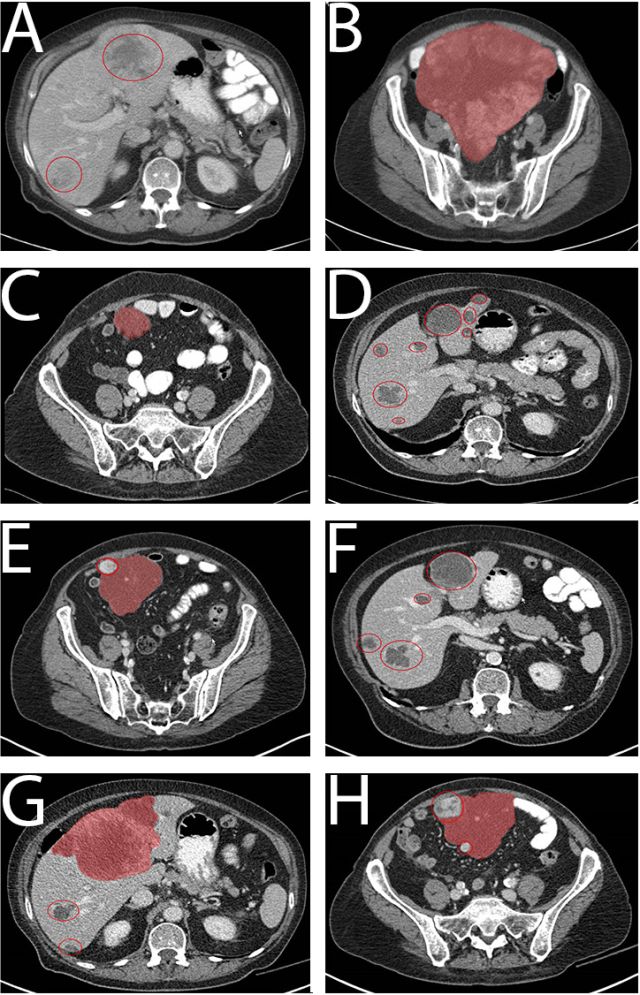

一例74岁患有原发性十二指肠间质瘤(GIST)的女性患者因心源性休克收入我院急诊科,死于心外肿瘤破裂导致的心脏骤停。冠状动脉CT血管造影(图A)显示肿瘤有来自右冠状动脉和左前降支的营养血管。心血管磁共振(图B)显示肿瘤(箭头)具有不均匀强化,起自心肌。患者选择接受保守治疗。尸检于心室浆膜下检测到一个7×8×7厘米的弹性软肿瘤。病理示呈纤维样增生的轻度非典型梭形细胞(图C),CD117(c-kit)阳性(图D)。因此,该心外肿瘤被诊断为GIST转移。虽然三分之二的GIST转移患者为肝转移,心脏转移较罕见。